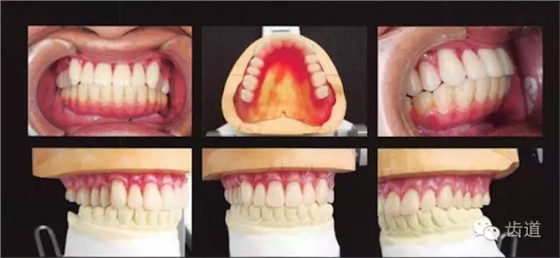

看阿部老師怎么做? 1、與患者充分溝通治療的難點和可能出現(xiàn)的問題 2、上頜用松軟牙齦的印模技術(shù),由后方按壓,使松軟的部分立起,取無壓力開窗式印模 3、加厚前牙區(qū)的邊緣厚度,使之在前鼻嵴處獲得支撐 4、做好后緣封閉 5、人工牙怎么排列才能穩(wěn)定? 前牙按正常覆he覆蓋進(jìn)行排列 雙尖牙內(nèi)收,排列在牙弓的穩(wěn)定區(qū)間 咬合平面只能按無法修正的下頜種植義齒進(jìn)行排列 6、繼續(xù)在口內(nèi)試咬,逐一調(diào)整每個牙的位置,以防止義齒的翹動和不穩(wěn)定 7、最終的義齒采用舌側(cè)集中he型 阻止翻復(fù)的排牙方式 選擇高精度的義齒聚合方法 前牙唇側(cè)基托保持有支撐作用的厚度 容易形成支點的區(qū)域以組織調(diào)整劑(TC)進(jìn)行調(diào)整 完全適應(yīng)后,將襯墊的極小區(qū)域置換成常溫聚合樹脂 8、義齒配戴完成 多虧患者的咀嚼方式良好,義齒戴入后既不疼痛,也不會脫落!